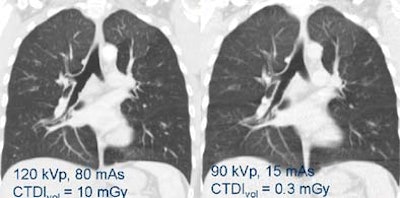

![]() |

| Low-dose CT reveals even very small pulmonary emboli. Images courtesy of Dr. Mathias Prokop. |

| Even extremely low-dose imaging can often answer the relevant clinical questions, especially in high-contrast areas such as the lungs. Image at right was acquired with 1/30th the dose of example at left; both reveal air trapping. Images courtesy of Dr. Mathias Prokop. |